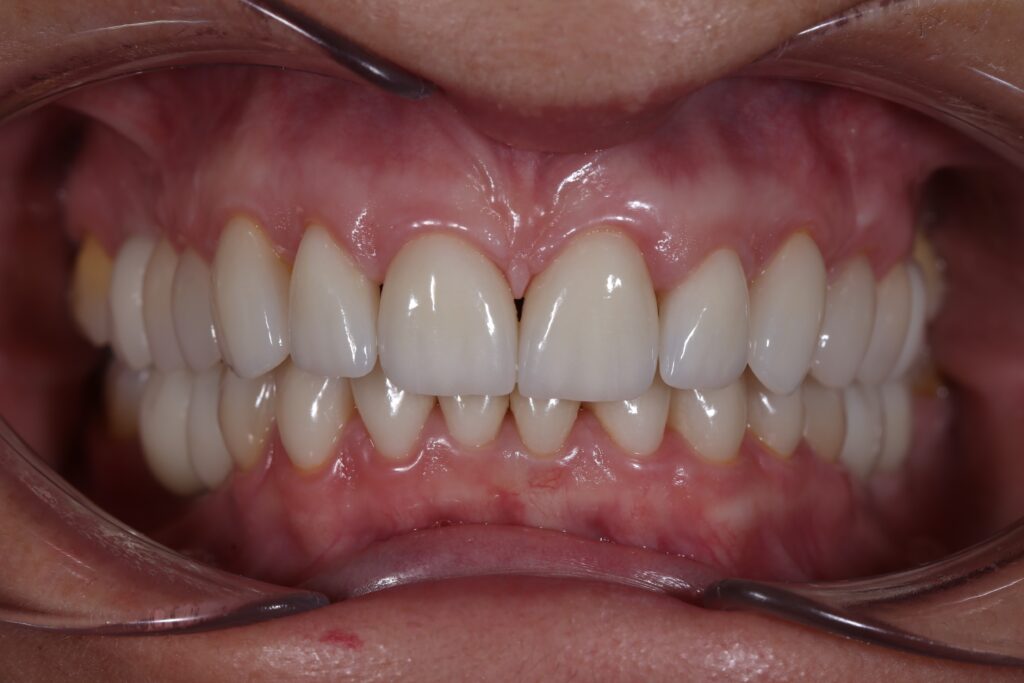

Этап имплантации и протезирования и результаты

Затем были установлены имплантаты Megagen AnyOne.

Спустя 3 месяца после установки имплантатов была произведена замена несостоятельных реставраций и пломб для избежания развития вторичного кариеса под винирами и коронками.

Сделано препарирование зубов на верхней и нижней челюстях с контролем глубины (0.7-0.8 мм) под керамические реставрации. Сняты оттиски с имплантатов.

Установлены временные виниры и коронки из пластика. Спустя 26 дней были зафиксированы керамические виниры и коронки на своих зубах и циркониевые коронки на имплантатах.